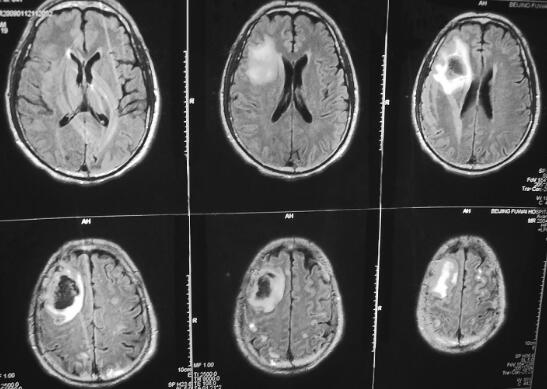

诊治经过:患者入院后仍发热,体温37.8~39.2℃,意识淡漠,嗜睡状态,1月5日行脑CT示右侧额叶脑白质内小片状低密度影。1月12日MRI示颅内多发病灶,不除外颅内额叶血肿合并颅内多发感染灶(图2、图3),行3次血培养均为金黄色葡萄球菌,给予利奈唑胺0.6g,ivgtt,每12小时1次及左氧氟沙星0.2g,ivgtt,每日2次静点治疗,并同时给予营养支持及对症治疗,约1周后患者体温逐渐降至正常,体温正常后继续给予利奈唑胺静点治疗4周,患者未再发热,二尖瓣为中量反流,心脏不大,可暂不予手术治疗,继续随访。

图2 2009年1月12日入院时,头颅MRI示颅内多发病灶

图3 2009年1月12日入院时,头颅MRI示颅内多发病灶